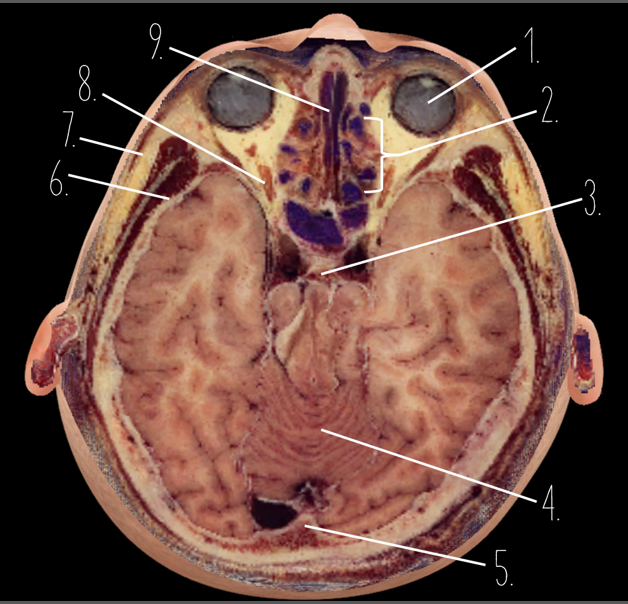

1?

Globe of Eye

2?

Ethmoid Sinus

3?

Pituitary Gland

4?

Cerebellum

5?

Internal Occipital Protuberance

6?

Wing of Sphenoid

7?

Zygomatic Arch

8?

Optic Nerve

9?

Vomer